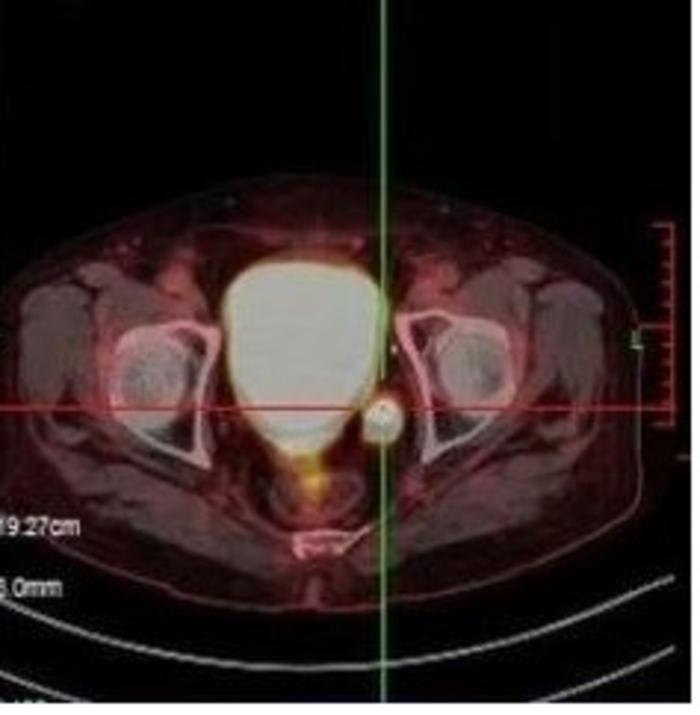

3.PSMA-SPECT/CT的应用及优势

PSMA-SPECT/CT技术是一种前列腺特异性膜抗原-单光子发射计算机断层摄影术,联合同机CT扫描图像融合技术的检查,与目前影像学检查比较,能够更好地发现前列腺癌转移灶,且精准指导靶病灶治疗,进而使患者获益。

PSMA-SPECT/CT检查也能够在PSA较低水平时精确发现盆腔淋巴结转移灶,指导手术或药物治疗及其治疗后评价,应用PSMA-SPECT/CT技术,准确率也能78%以上。更关键的是PSMA-SPECT/CT非常便宜,在上海肿瘤医院,该项检查仅1350/次,而PSMA PET-CT在上海的收费标准是7000/次。从性价比以及长期的治疗后定期随访来看PSMA-SPECT/CT的优势明显。